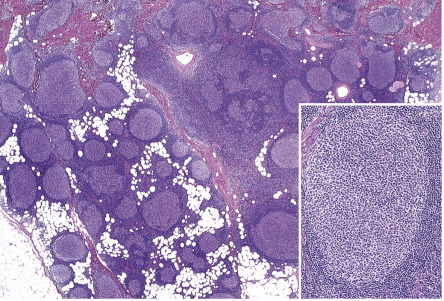

Histology of PCMZL shows a patchy, nodular or diffuse infiltrate involving the dermis and subcutaneous fat. The epidermis is spared. A characteristic pattern can be observed at scanning magnification ( Fig. 119.8A ): nodular infiltrates (sometimes containing reactive germinal centers) are surrounded by a pale-staining population of small- to medium-sized cells with indented nuclei, inconspicuous nucleoli, and abundant pale cytoplasm – variously described as marginal zone cells, centrocyte-like cells, or monocytoid B cells ( Fig. 119.9A ) . In addition, plasma cells (at the margins of the infiltrate), lymphoplasmacytoid cells, small lymphocytes, and occasional large blasts are observed. Eosinophils are also a common finding. In some patients, there may be a granulomatous reaction with epithelioid and giant cells. Cases with a predominance of lymphoplasmacytoid lymphocytes were once classified as cutaneous immunocytomas, but are now considered variants of PCMZL. PAS-positive intranuclear inclusions (Dutcher bodies) are sometimes observed and represent a valuable clue to the diagnosis ( Fig. 119.9B ). Occasionally, the predominant cell type is a plasma cell ( Fig. 119.9C ), and although such cases used to be classified as primary cutaneous plasmacytomas, they are now also considered to be variants of PCMZL . Finally, rare cases are characterized by the predominance of large blastoid cells resembling plasmablasts ( Fig. 119.9D ) .

The centrocyte-like cells stain positively for CD20, CD79a, Fc receptor-like 4 (FCRL4/IRTA1) , and Bcl-2; they are negative for CD5, CD10, and Bcl-6. In the overwhelming majority of cases, intracytoplasmic monotypic expression of immunoglobulin light chains (either κ or λ, but not both) can be observed ( Fig. 119.10 ). The monoclonal population of B lymphocytes is often characteristically arranged at the periphery of the cellular aggregates ( Fig. 119.8B ). Staining for proliferation markers also shows increased positivity at the periphery of the nodules (as well as in reactive germinal centers) ( Fig. 119.8C ). IgG4 expression is observed in a minority of cases with plasmacytic differentiation but is not associated with systemic IgG4-related disease . Monoclonal rearrangement of IGH can be detected in the majority of cases (60–80%).